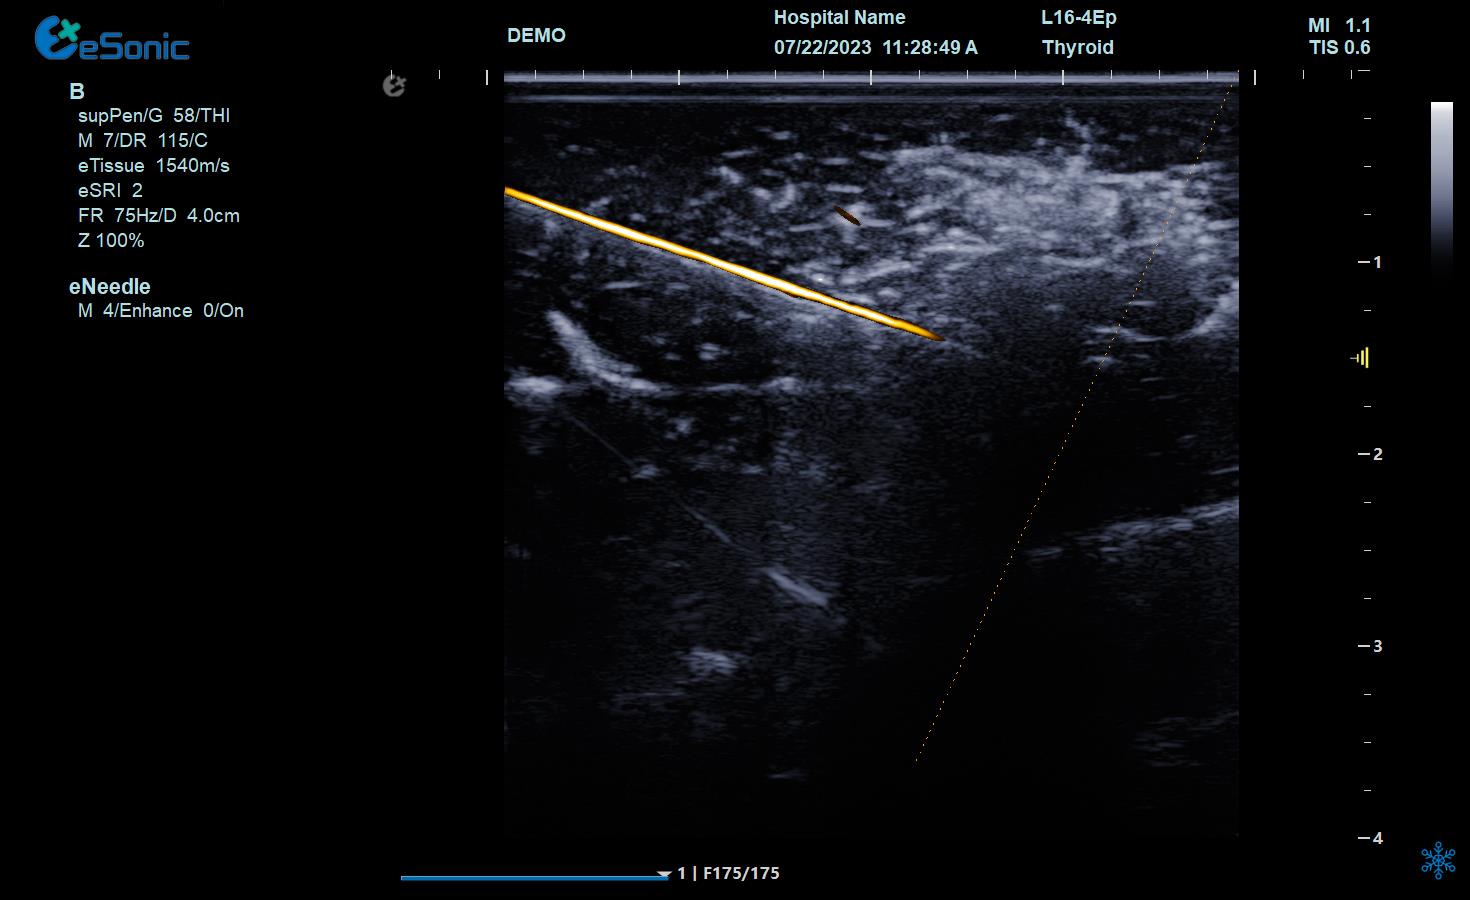

空化组织里消融针智能map